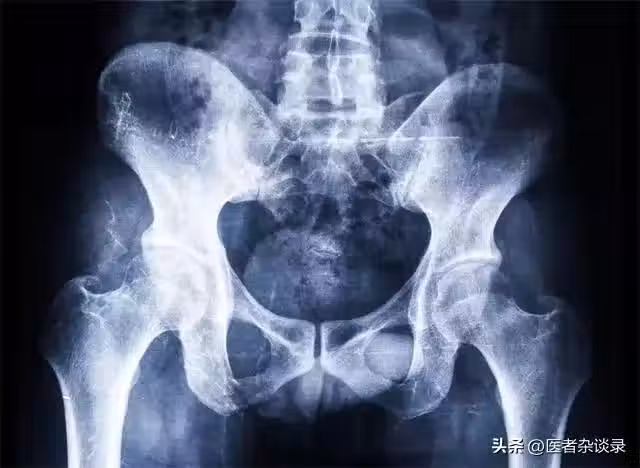

胯骨,作為人體承重和運動的重要部位,一旦出現問題,往往會影響我們的行走、坐姿乃至日常的生活。胯骨疼痛並非小事,它可能是身體發出的「求救」信號,提示我們可能患有某些疾病。